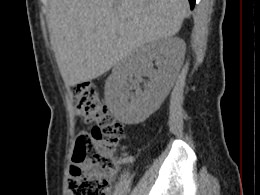

Мультиспиральная компьютерная томография почек и мочевыводящих путей является высокоинформативным методом исследования, основанном на использовании воздействия рентгеновских лучей на органы и ткани человека. Методика предусматривает послойное сканирование области почек, мочевыводящих путей и получение снимков исследуемой области в мельчайших подробностях.

Для улучшения визуализации патологических очагов в некоторых случаях дополнительно применяется контрастное усиление. Для этого пациенту внутривенно вводится йодсодержащее контрастное вещество, которое накапливается в патологически измененных участках и вызывает их яркое контрастирование на фоне здоровых тканей.

МСКТ почек и мочевыводящих путей с контрастированием позволяет выявить опухолевые образования на ранних стадиях, отличить доброкачественную опухоль от злокачественной, определить размеры опухоли, точную локализацию и степень распространения в окружающие ткани. Компьютерная томография почек с внутривенным болюсным контрастированием необходима для определения тактики лечения и объема оперативного вмешательства.